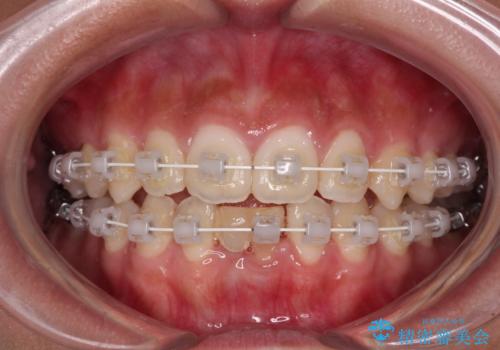

- 矯正装置

- 審美装置

ワイヤー装置により矯正治療を行うとともに舌突出癖改善のためのトレーニングをしっかりと行っていただき、咬み合わせが安定した位置となったタイミングで下顎前歯にブリッジの仮歯を装着していく計画としました。